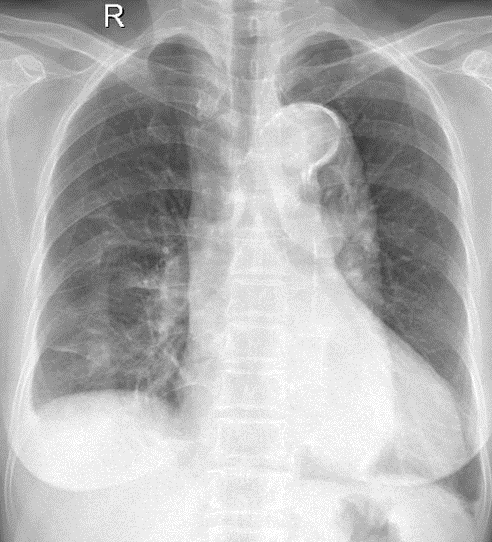

1-Xơ thùy giữa và thùy dưới phổi (P) 2-Tràn dịch màng phổi (P) lượng ít 3-Cung động mạch chủ dãn 4-Cung động mạch chủ đóng vôi 5-Tim (T) lớn